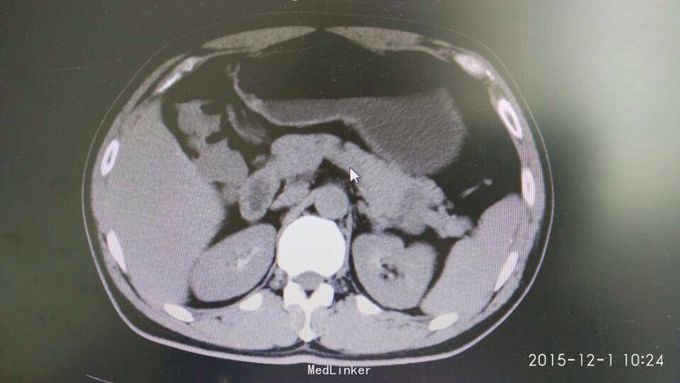

胃间质瘤 拟行胃间质瘤切除术

瘤体较大,超过5cm,术中注意与胰腺关系,如果压迫胰腺或压迫脾脏血管,是否考虑部分胰腺切除及脾切除,是否考虑胃空肠吻合。